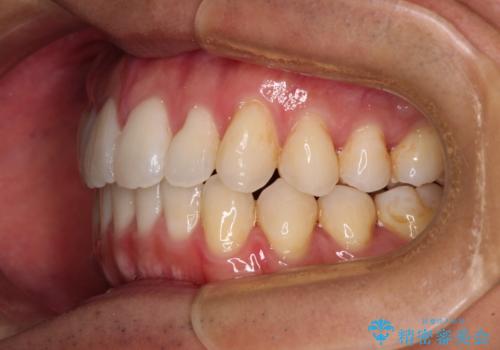

- 全体的なデコボコと、前歯の前に出ている感じを気にして来院された患者様です。

患者様と相談の上、非抜歯にてインビザラインを用いて矯正治療を行うこととし、IPR(歯と歯の間)並びに歯列全体の後方移動により口元の突出感の改善することとしました。

お仕事が忙しい方で、装着時間が不足したり、定期的な通院ができなかったりと、自己管理が重要なインビザラインによる矯正治療が長期化する要因が重なり、5年ほどの期間を要しました。